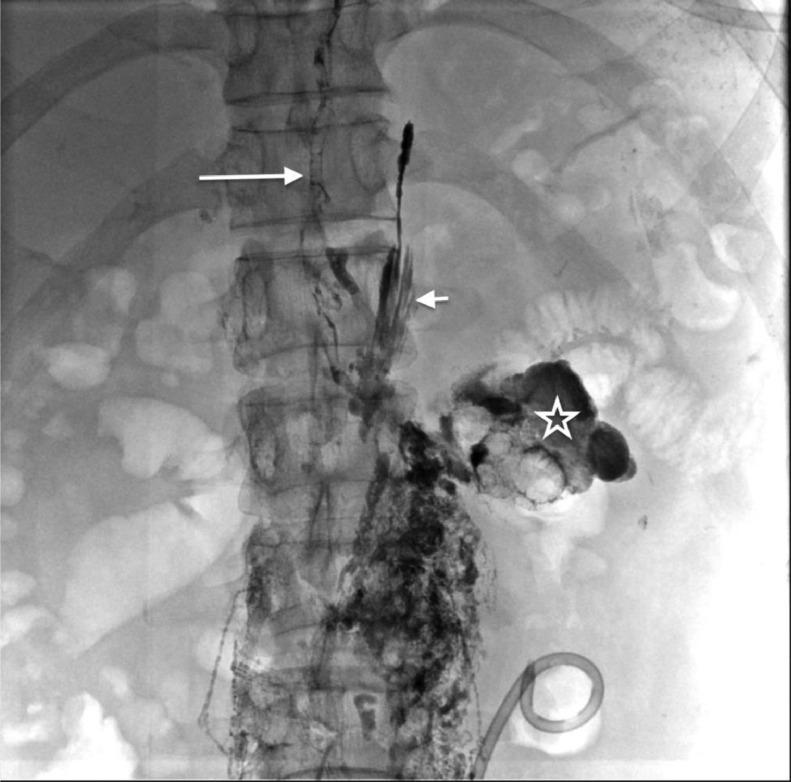

Chylous ascites results from the leakage of lipid-rich lymphatic fluid into the peritoneal cavity. Most postsurgical chylous ascites occurs following abdominal aortic surgeries. However, rarely, it is a complication after laparoscopic donor nephrectomy. Postsurgical chylous ascites are often managed with conservative treatment or surgery, but lymphatic embolization may be required. Here, we presented a 45-year-old male patient who was referred for abdominal distension for 1 week after left donor nephrectomy. The drain fluid was milky and fluid analysis revealed high concentrations of triglycerides and chylomicron, confirming diagnosis of chylous ascites. The patient was treated with conservative therapy including a low-fat diet and fluid drainage but continued to have high draining output (up to 1500-2000 mL/24 h). He underwent magnetic resonance lymphangiography and intranodal lymphangiography, revealing extravasation of contrast into the abdomen and the left renal fossa. We embolized the interstitial lymphatic of the left retroperitoneal and lymphatic vessels leak. The patient was discharged from hospital at the fifth day after intervention. In this article, we demonstrate lymphatic lesions, the safety, and success of this technique.

乳糜性腹水是由于富含脂质的淋巴液漏入腹腔所致。大多数术后乳糜性腹水发生在腹主动脉手术后。然而,腹腔镜供体肾切除术后很少出现这种并发症。术后乳糜性腹水通常采用保守治疗或手术治疗,但可能需要进行淋巴栓塞。在此,我们报告了一名45岁男性患者,他在左供体肾切除术后1周因腹胀前来就诊。引流液呈乳白色,液体分析显示甘油三酯和乳糜微粒浓度很高,确诊为乳糜性腹水。患者接受了包括低脂饮食和液体引流在内的保守治疗,但引流液量持续很高(高达1500 - 2000毫升/24小时)。他接受了磁共振淋巴管造影和结内淋巴管造影,显示造影剂渗入腹部和左肾窝。我们对左腹膜后间隙淋巴管和淋巴管漏进行了栓塞。患者在干预后第五天出院。在本文中,我们展示了淋巴病变以及该技术的安全性和成功性。